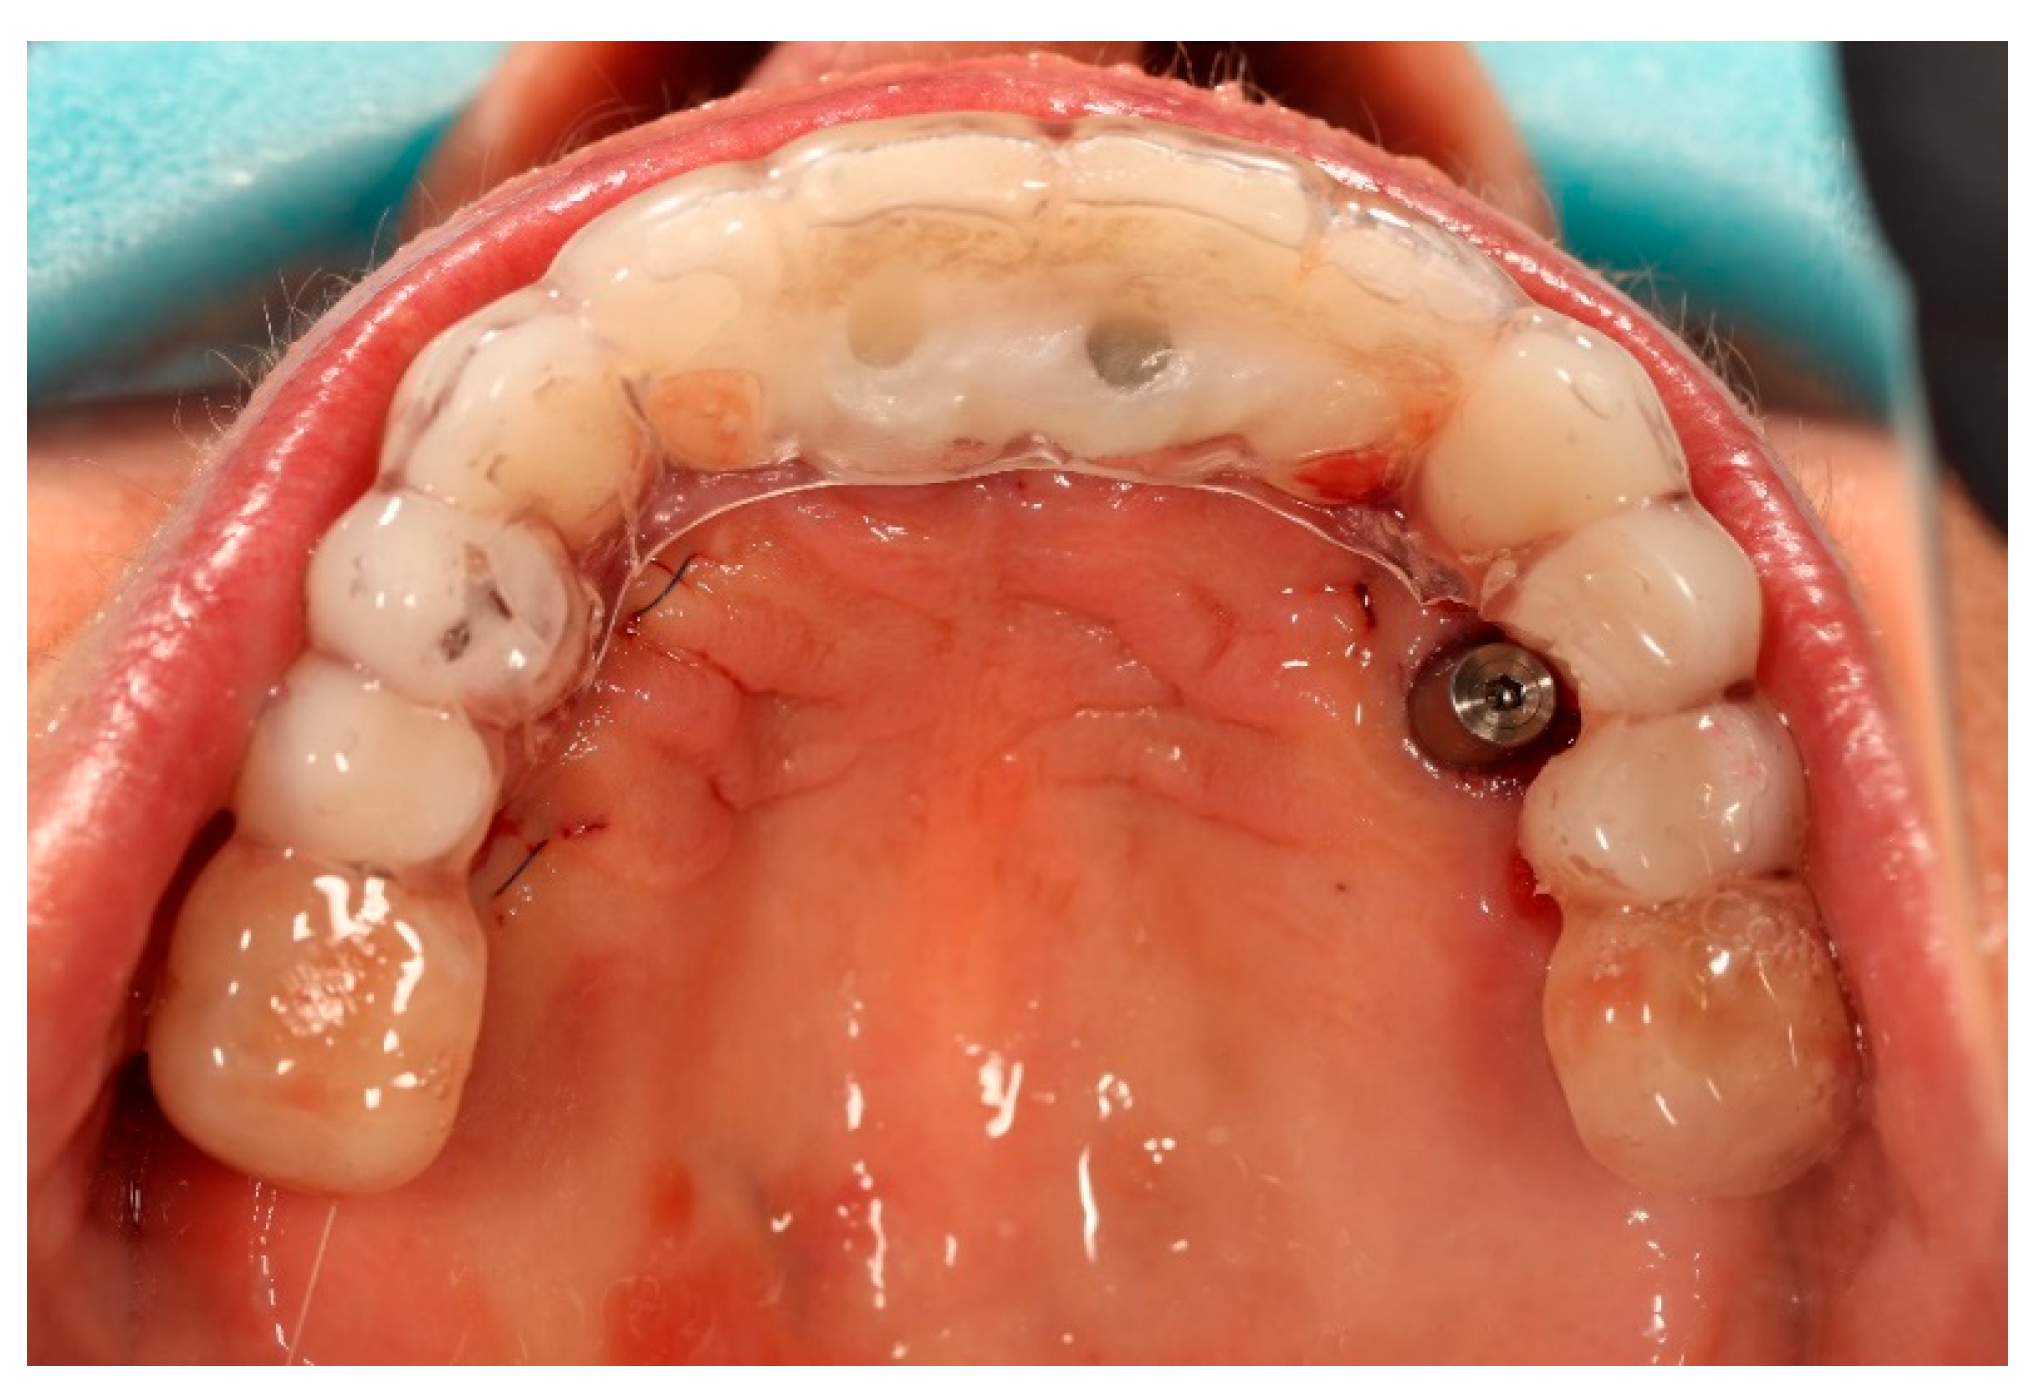

The next appointment was scheduled after 24 h. At the 24 h follow-up, the clinical situation was considered appropriate for proceeding with the provisional restoration. The existing prosthetic restorations were unscrewed from the implants, and the previously selected multi-unit abutments were mounted on all four supporting implants, excluding the newly placed ones, where the closing caps were removed.

Based on the merged datasets (biocopy + SmartFlags® scan), the provisional screw-retained, implant-supported full-arch prosthesis was designed in Exocadsoftware (Exocad GmbH, Darmstadt, Germany) and subsequently fabricated using OnX Tough 2 resin (SprintRay Inc., Los Angeles, CA, USA) by means of 3D printing. The intaglio (tissue-facing) surface was polished [18], while the labial surface was characterised and glazed to improve aesthetics (Optiglaze Clear, GC International AG, Luzern, Switzerland). As demonstrated in the accompanying clinical photographs, minor superficial cracks in the glaze layer are visible on the external surface of the prosthesis (Figure 8).

Finally, the prosthesis was delivered by fixing to the multi-unit abutments with screws. Clinical adjustments were performed to ensure perfect fit, occlusion, phonetics, and aesthetics. The patient reported immediate improvement in comfort and satisfaction compared to the acrylic splint (Figure 9 and Figure 10).

Figure 9. Digitally planned, 3D-printed full-arch provisional restoration delivered early and fixed to the multi-unit abutments with screws, shown in situ (occlusal view).